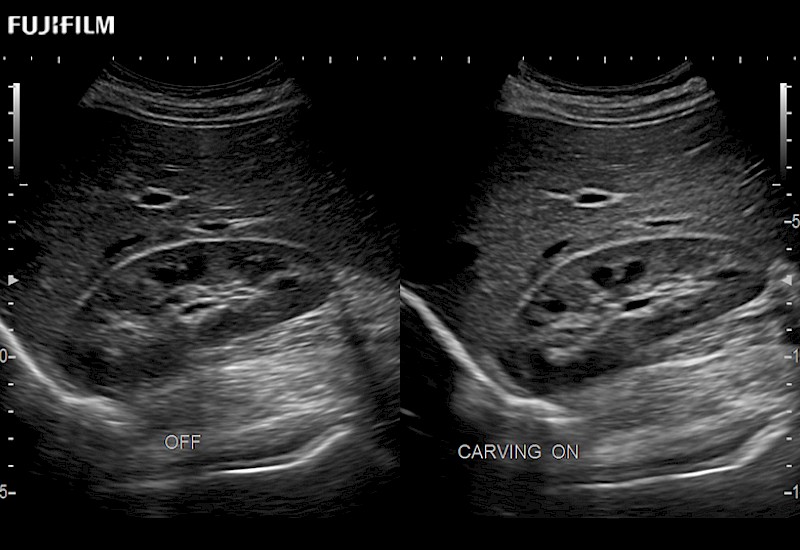

The ARIETTA 750 incorporates all of the proven technologies and functions that medical professionals have come to expect from Fujifilm Healthcare.

ARIETTA 750 is the definitive diagnostic ultrasound solution for any clinical setting - Private Office, Imaging Center, or Hospital. The ARIETTA platform provides the ultimate in clinical performance with its state-of-the-art features and large user-friendly display.

The ARIETTA 650 DI combines trusted Fujifilm Healthcare technologies and features tailored for surgical oncology.

Designed to meet the demands of surgeons, the ARIETTA 650 DI offers precise guidance. Its advanced capabilities and large, intuitive display offer accurate and efficient care in operating rooms and specialized surgical settings.